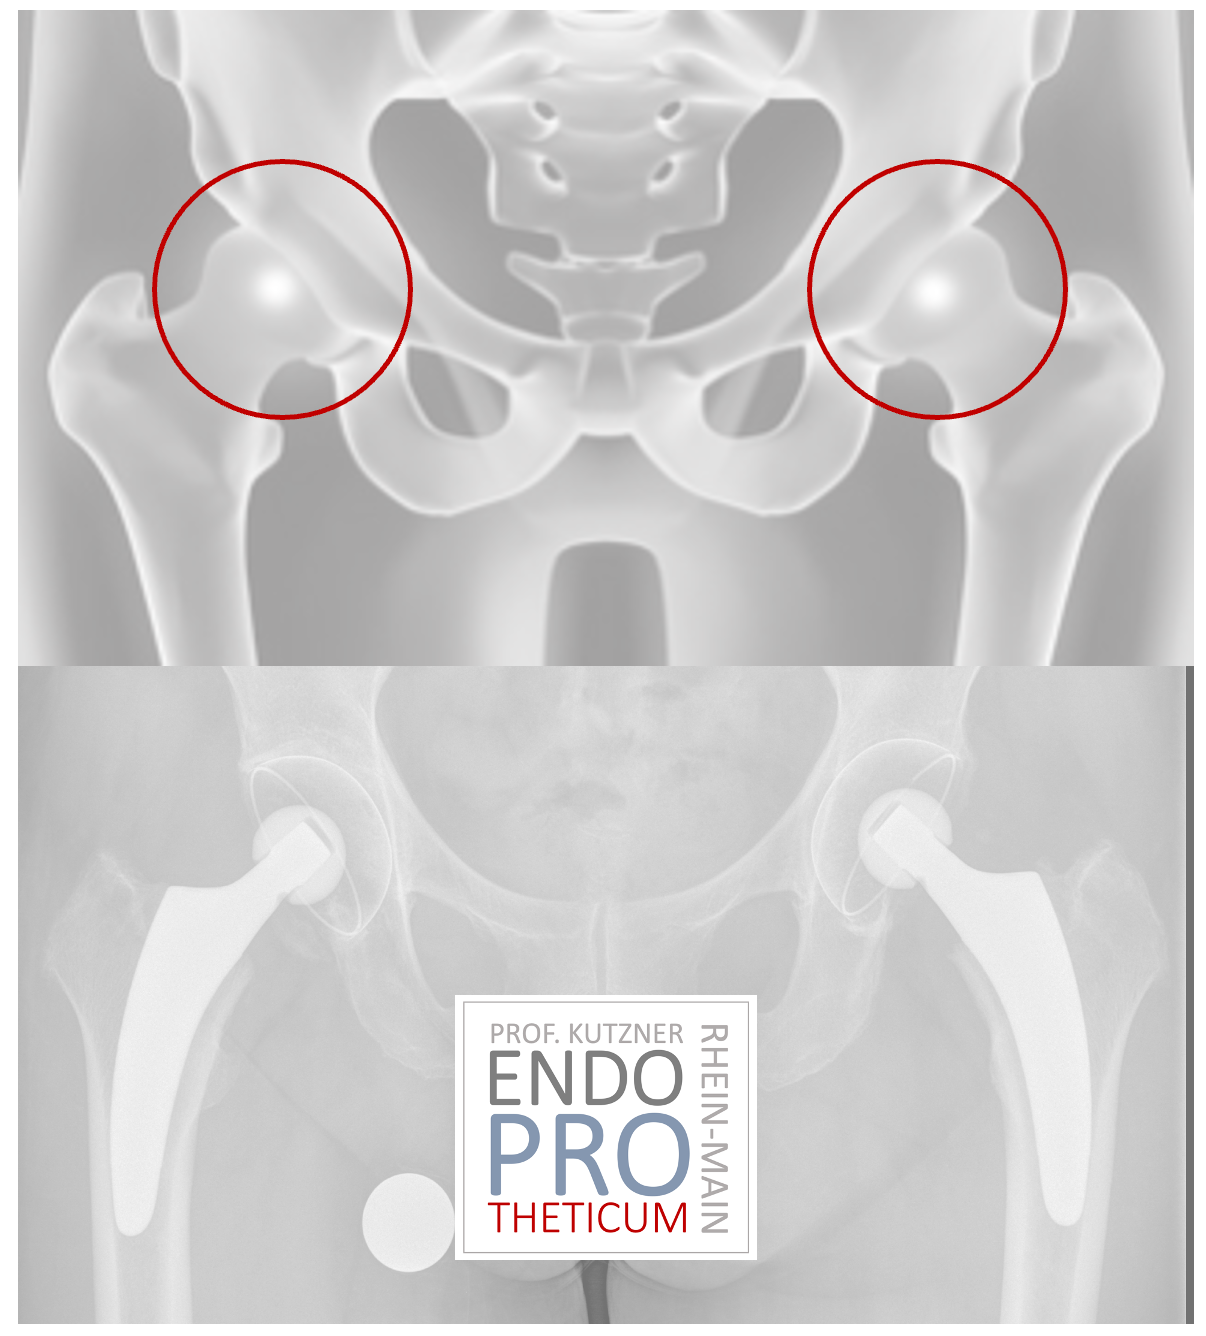

Las prótesis de eje corto se han vuelto cada vez más populares en los últimos años. La implantación de una PRÓTESIS de vástago corto tiene como objetivo preservar el hueso y crear condiciones favorables para su revisión sin cambiar los conceptos básicos de la artroplastia de cadera convencional.

El concepto de vástagos cortos modernos guiados por calcar en la artroplastia de cadera tiene como objetivo la reconstrucción precisa de la geometría anatómica individual de la cadera. Se utiliza una técnica de implantación respetuosa con los huesos y los tejidos blandos junto con una carga fisiológica en la parte del fémur cercana a la articulación para preservar el hueso a largo plazo.